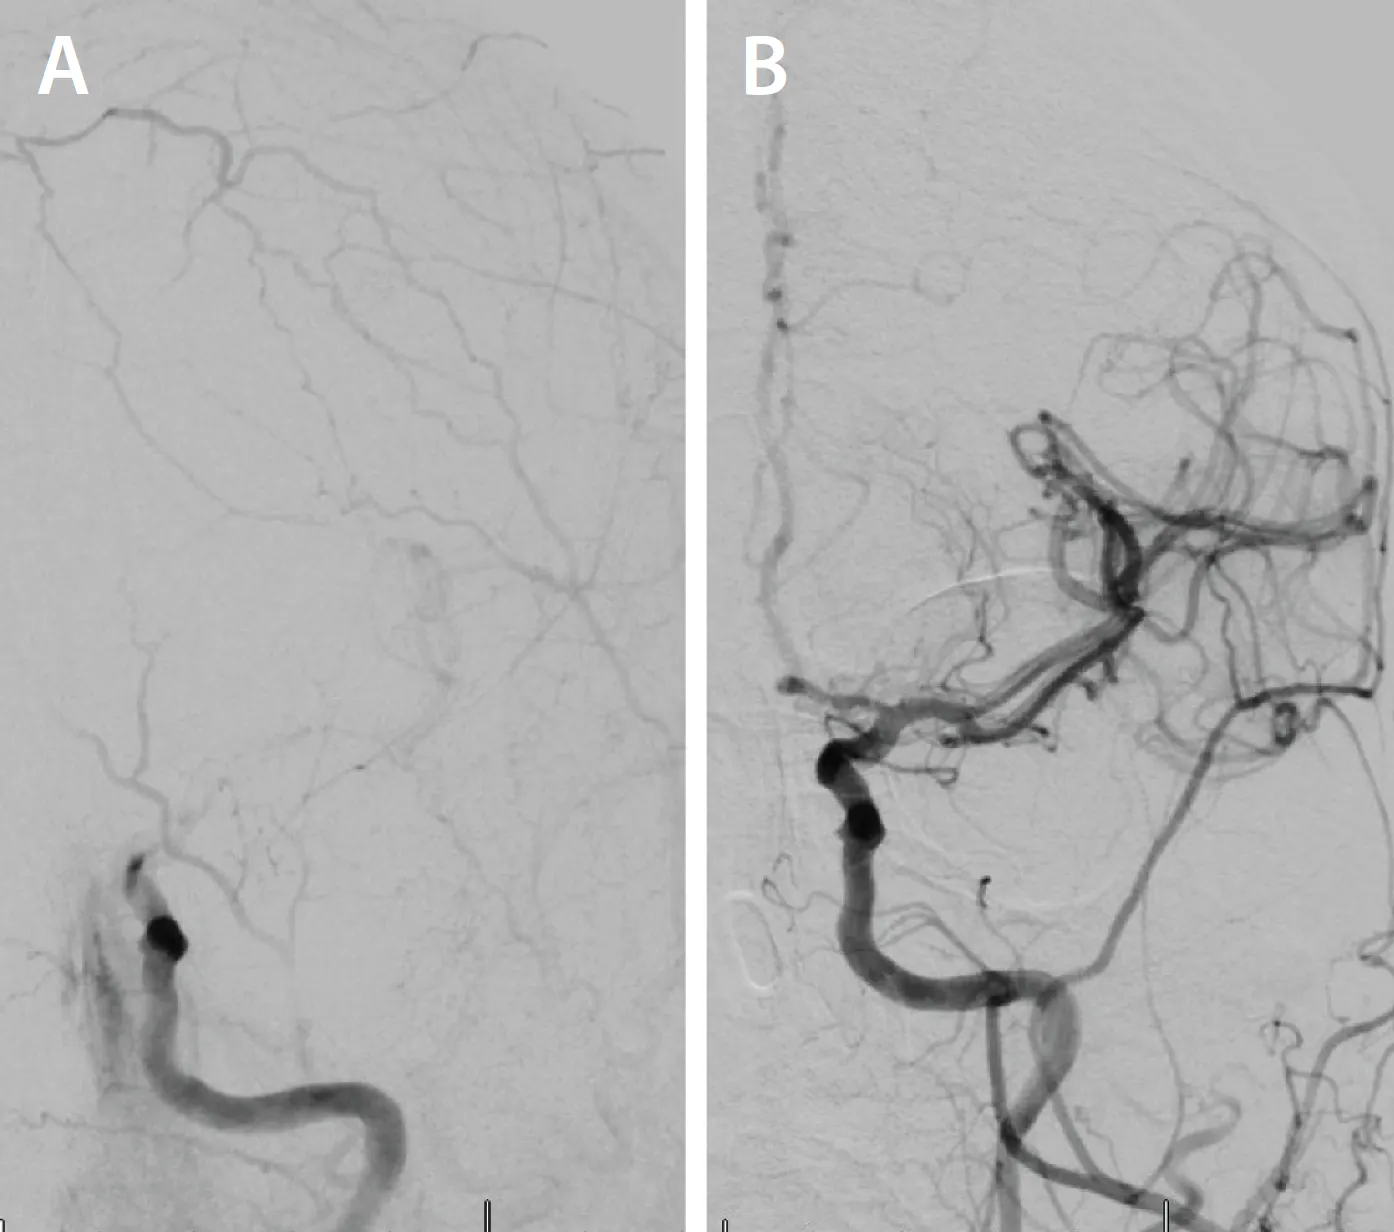

After ultrasound-guided transfemoral access, the patient was systemically heparinized. An aortic arch angiogram demonstrated a bovine, type II arch configuration. The CCA was selectively cannulated using a Van Schie 4 catheter (Cook Medical) and Glidewire® (Terumo Interventional Systems). Angiography confirmed a critical focal stenosis at the distal anastomosis of the bypass graft (Figure 2A). For enhanced stability, a 7-F Destination™ sheath (Terumo Interventional Systems) was advanced into the proximal CCA. A distal filter wire was then carefully navigated across the lesion and deployed in the distal ICA. A 10- X 20-mm Roadsaver™ dual-layer micromesh carotid stent (Terumo Interventional Systems) was advanced and deployed across the anastomotic stenosis. Postdilation was performed using a 5- X 40-mm angioplasty balloon to optimize luminal expansion and stent apposition. Completion angiography demonstrated an excellent result, with no residual stenosis, preserved distal flow, and no angiographic evidence of embolization (Figure 2B). The filter was retrieved and was free of visible debris, and the patient experienced no periprocedural neurologic events.

Figure 2. Selective angiography of the left carotid artery showing a focal severe luminal stenosis > 80% (A). Completion angiography post Terumo Roadsaver carotid stent demonstrating no residual stenosis (B).